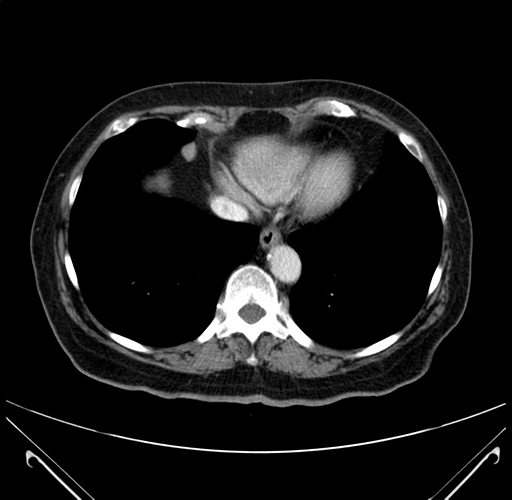

Pre-Chemo: Coronal Venous

Coronal Venous